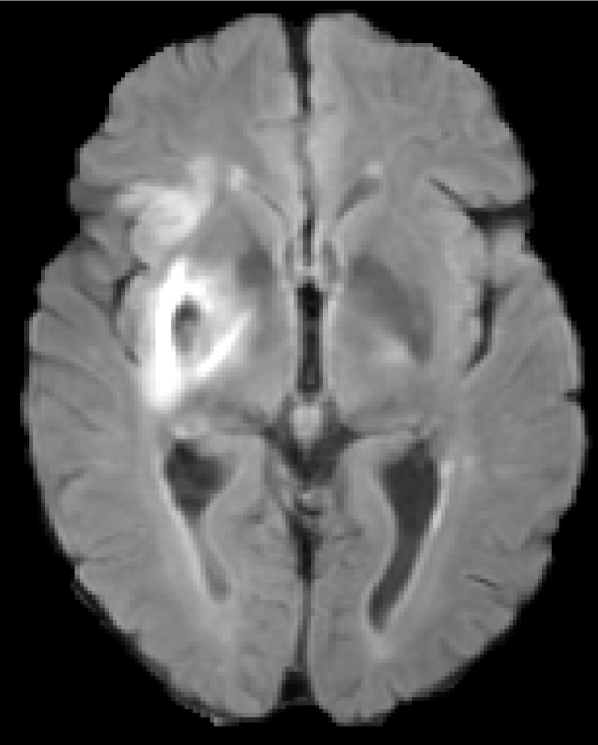

Figure 5 shows qualitative results of four representative segmentation examples from the proposed method. In general, the majority of the lesion is correctly segmented with minor border and small hole inaccuracies as seen in cases 11 and 26. Other less typical errors include under or oversegmentation of the lesion, as seen in case 2 where false positives are found on the upper part of the lesion. In the example of case 15, the lesion is undersegmented due to a confounding unusual appearance of some parts.

Refer to caption

(a) Case 2

(b) Case 11

(c) Case 15

(d) Case 26

Figure 5: Output segmentation masks of representative cases from the training images of ISLES 2015 SPES dataset. On all images, true positives are denoted in green, false positives in red and false negatives in blue.